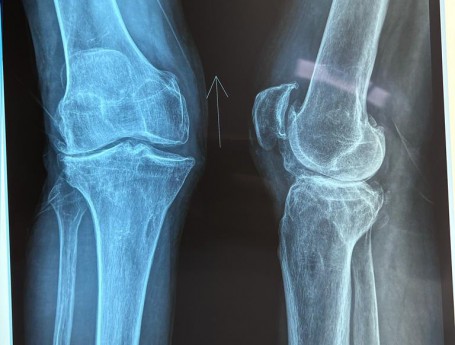

Total Knee Arthroplasty on a severe Genu Valgum

• Total Knee Arthroplasty on a severe Genu Valgum